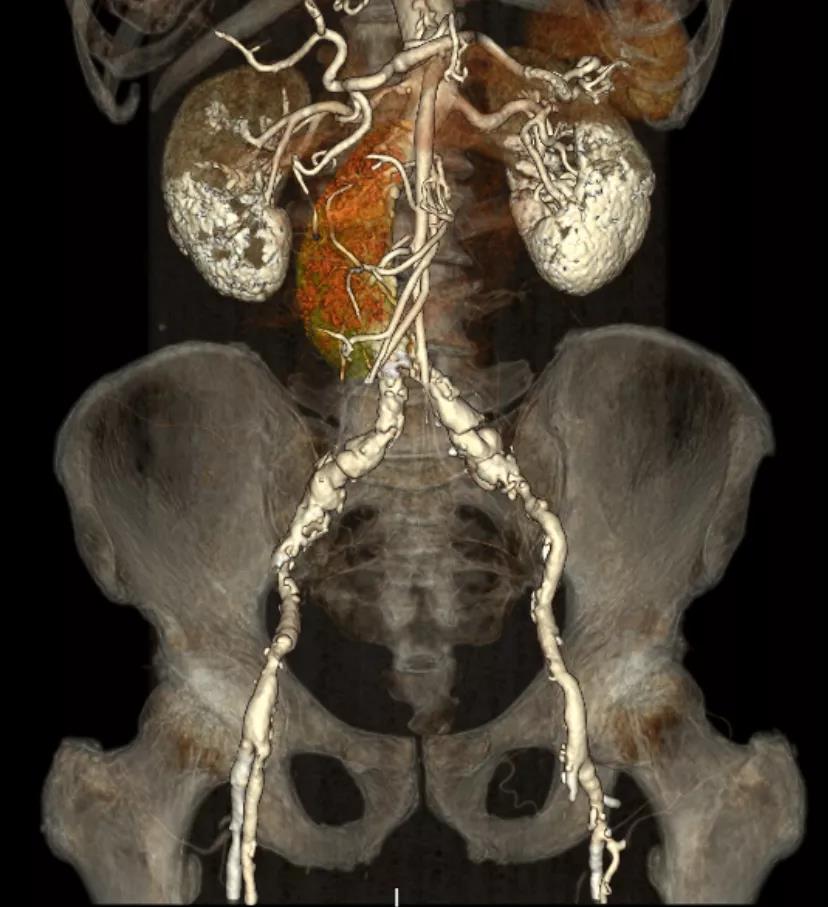

CT重建显示患者双侧髂动脉、股动脉、锁骨下动脉质量极差,多发钙化狭窄伴局部夹层,无法经股动脉和锁骨下动脉入路。而且患者重度肺气肿致心脏两侧受压,心尖被压缩在胸骨及肋弓骨性融合后方,亦无法经心尖入路。评估双侧颈动脉近端均有钙化斑块伴轻度狭窄,平均管径约6mm,左侧管径略大于右侧。颅内Willis环交通支通畅,可以耐受经单侧颈动脉介入手术。

髂动脉、股动脉状况极差